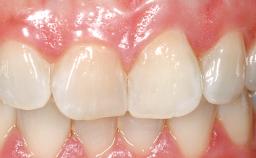

Immediate Flapless Placement of an Implant in a Maxillary Right Lateral Incisor Site

This 43-year-old male patient, a non-smoker, came to our practice because of a fracture of tooth 12 caused by a bicycle accident. Due to the combined para- and infrabony crown and root fracture, tooth extraction, and subsequent implant placement were suggested to the patient as the therapy of choice. The patient had high esthetic expectations with regard to the treatment outcome and asked for an immediate fixed provisional restoration. His individual esthetic risk profile summed up to a medium esthetic risk.

Patient's Esthetic Expectations Low Medium High

Lip Line No exposure of papillae Exposure of papillae Full exposure of mucosa margin

Periodontal Phenotype Low-scalloped, thick Medium-scalloped, medium-thick High-scalloped, thin

Soft Tissue Contour and Volume Ideal